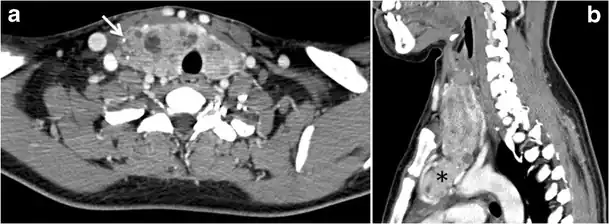

Fig. 4. A 45-year-old male patient presented with anterior mediastinal metastatic PTC lesions and occult primary on imaging. Histopathology examination of the resected thyroid gland revealed micro-foci of PTC; the largest, in the isthmus, measured 4 mm. a transverse greyscale ultrasound of the thyroid demonstrates homogeneous gland with normal echogenicity and size. No focal lesion or micro-calcifications. b Non-enhanced CT scan obtained as part of PET/CT examination shows a heterogeneous, large, relatively dense anterior mediastinal mass (white arrow) with peripheral calcification (arrowheads). Thyroid gland has normal CT appearance with no abnormal FDG uptake (not shown).[1]

Fig. 13. A 27-year-old female patient known to have goiter. a, b Axial and sagittal enhanced CT scan images of the neck demonstrate a heterogeneously enhancing, enlarged thyroid gland with scattered calcifications (white arrow), cystic changes, and substantial retro-sternal extension (black asterisks). No lymphadenopathy or substantial airway narrowing.[1]